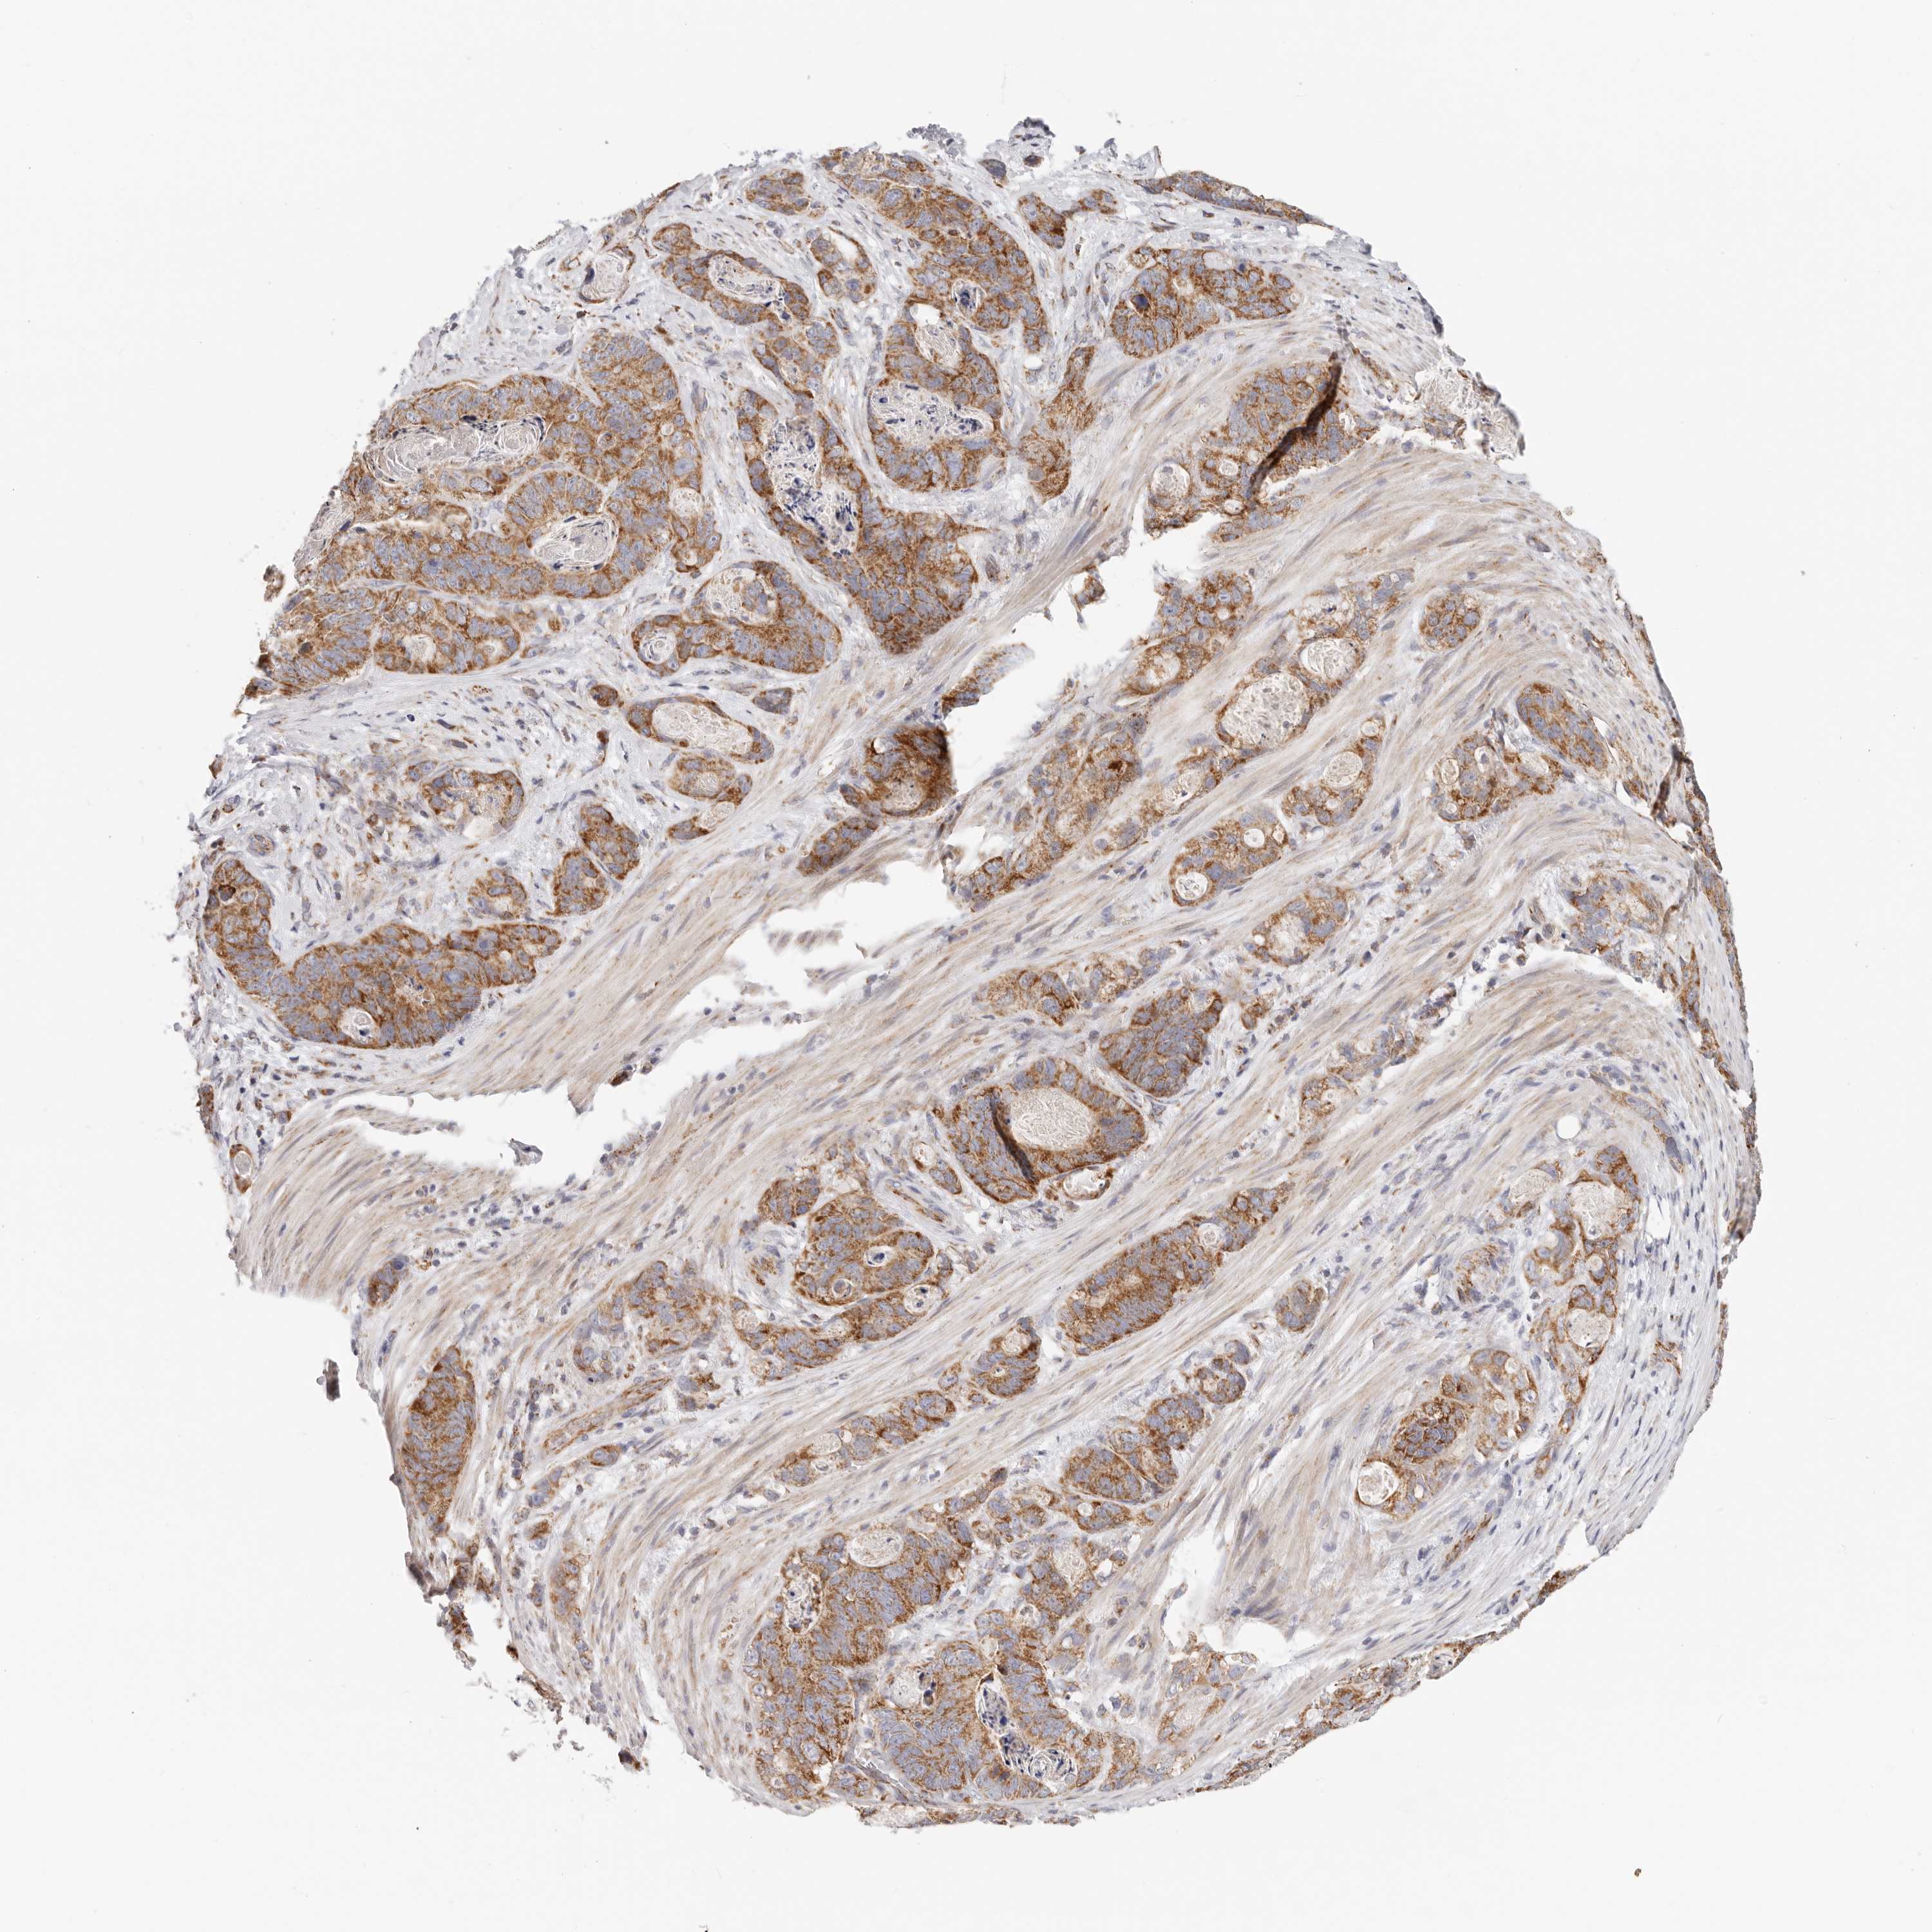

STOMACH CANCER - Protein expressioni

A mouse-over function shows sample information and annotation data. Click on an image to view it in a full screen mode. Samples can be filtered based on level of antibody staining by selecting one or several of the following categories: high, medium, low and not detected. The assay and annotation is described here.

Note that samples used for immunohistochemistry by the Human Protein Atlas do not correspond to samples in the TCGA dataset.

Antibody stainingi

Antibody staining in the annotated cell types in the current human tissue is reported as not detected, low, medium, or high, based on conventional immunohistochemistry profiling in selected tissues. This score is based on the combination of the staining intensity and fraction of stained cells.

Each image is clickable and will lead to virtual microscopy that enables deeper exploration of all samples and also displays staining intensity scores, fraction scores and subcellular localization as well as patient and tissue information for each sample.

HPA030212

HPA030213

HPA030214

HPA030215

CAB013496

Adenocarcinoma, NOS